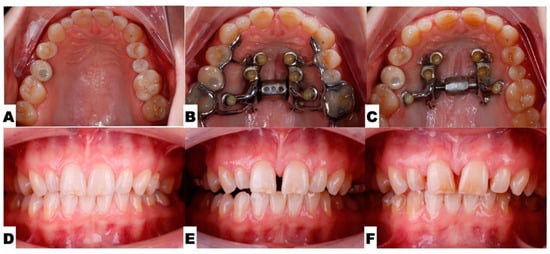

2. Materials and Methods

2.3. Procedures and Appliances

2.3.1. Surgical Protocol

2.3.4. Postoperative Assessment, Outcome Analysis, and Asymmetry Correction